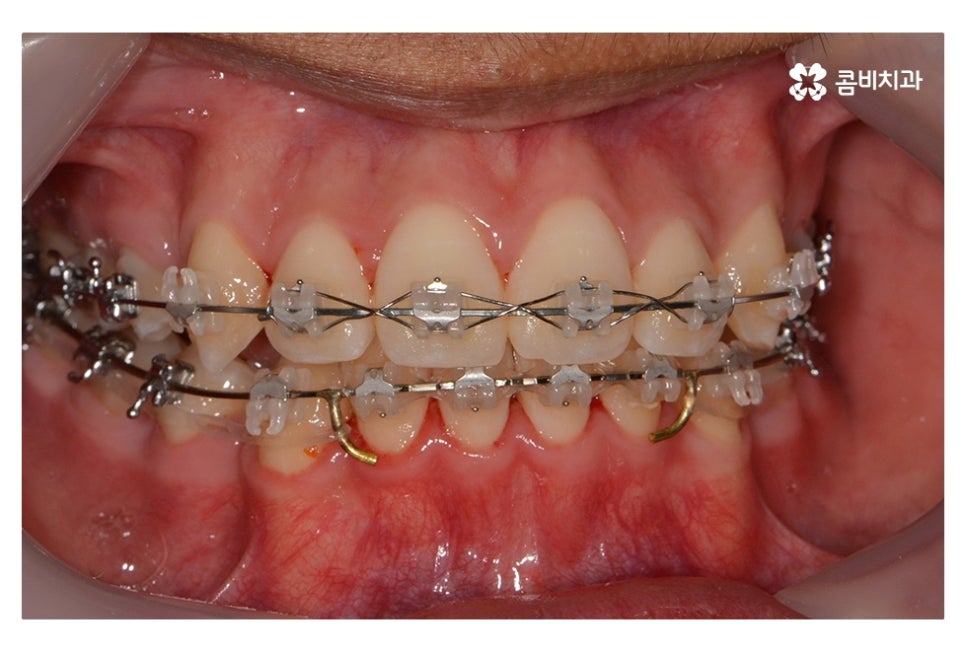

위 사진에서 보시면 시간이 지나면서 발치를 했던 치아의

공간이 사라지고 교정을 통해서 치열이 가지런해진 것을 확인할 수 있는데요.

중학생치아교정에 있어서 중요한 사항이 단지 치열만이

가지런해 보이는 것이 아닌 얼굴과의 조화와 교합이라 할 수 있어요.